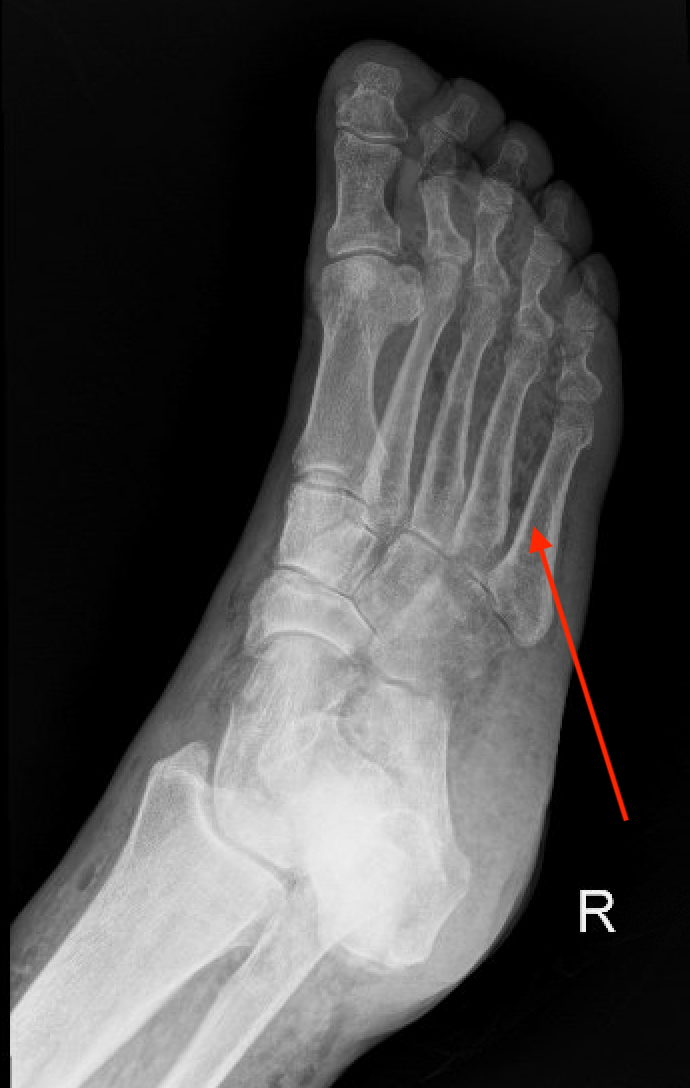

X-rays such as this example may demonstrate diagnostic subcutaneous air along the fascial plain but the sensitivity is only about 40%. High clinical suspicion should prompt a CT scan which has a 89% sensitivity for a necrotizing infection. 3